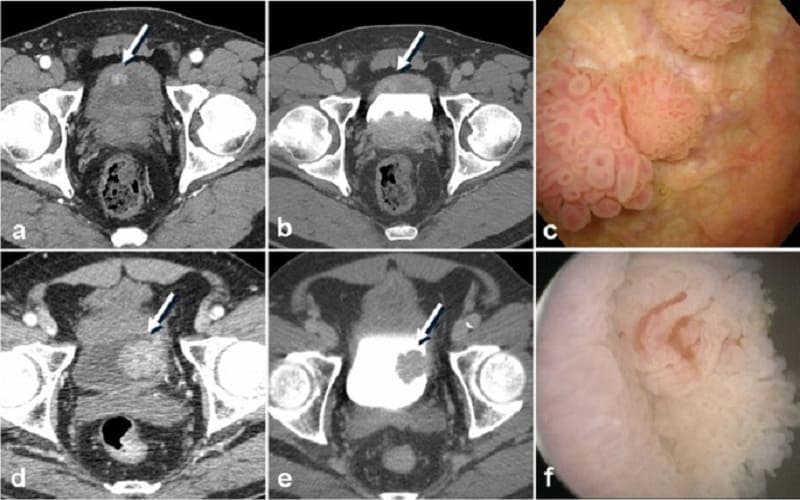

- Nội soi bàng quang: Đây là bước quan trọng nhất để chẩn đoán khối u bàng quang ở nam giới. Bác sĩ sử dụng một ống nội soi nhỏ đưa qua niệu đạo vào bàng quang để quan sát trực tiếp niêm mạc bàng quang và phát hiện khối u hoặc tổn thương bất thường.

- Sinh thiết hoặc cắt u qua nội soi (TURBT): Nếu phát hiện tổn thương nghi ngờ, bác sĩ sẽ lấy mẫu mô hoặc cắt khối u qua nội soi để làm xét nghiệm giải phẫu bệnh. Kết quả giúp xác định khối u là lành tính hay ác tính và mức độ xâm lấn.

- Chẩn đoán hình ảnh: Các phương pháp như CT urography, CT hoặc MRI có thể được chỉ định để đánh giá toàn bộ đường tiết niệu và xem khối u có lan rộng hay không. Siêu âm đôi khi được dùng để phát hiện bất thường ban đầu, nhưng không thay thế nội soi và sinh thiết.